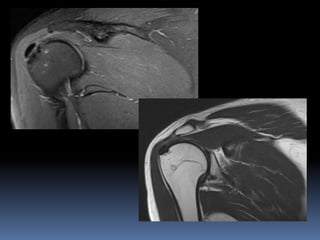

Key section in shoulder

coronal image in the

middle third

Anterior coronal section

Posterior coronal section shoulder

Sagittal section